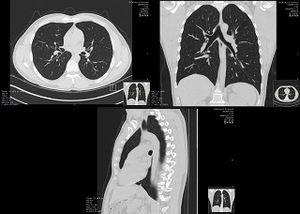

흉부에는 다양한 질병 또는 상태가 발생할 수 있는데, 흉막염, 연가슴, 무기폐, 흉통 등이 있다.[7] 이러한 상태는 유전적이거나 선천성 결함, 또는 외상으로 인해 발생할 수 있다.[7] 깊게 숨을 쉬거나 기침하는 능력을 저하시키는 모든 상태는 흉부 질환 또는 상태로 간주된다.[7]

흉부 손상(흉부 외상, 흉부 손상 또는 흉부 외상이라고도 함)은 미국에서 외상으로 인한 사망의 상당 부분을 차지한다.[7] 둔탁한 흉부 외상에서 발생하는 주요 병태생리는 공기 또는 혈액의 흐름, 또는 둘 다의 혼합에 대한 장애를 포함한다. 식도 천공과 같이 소화관 내용물의 누출로 인한 패혈증 또한 고려해야 한다. 둔탁한 외상은 일반적으로 흉벽 손상(예: 늑골 골절)을 유발한다. 이러한 부상과 관련된 통증은 호흡을 어렵게 만들 수 있으며, 이는 환기를 손상시킬 수 있다. 폐 타박상과 같은 직접적인 폐 손상은 주요 흉부 외상과 자주 관련되어 있으며 유사한 메커니즘으로 환기를 손상시킬 수 있다.

기흉은 공기 또는 가스가 흉막강에 축적될 수 있는 질환이다. 알려진 원인 없이 발생하거나 폐 질환 또는 급성 폐 손상의 결과로 발생할 수 있다.[10] 기흉의 크기는 공기 또는 가스가 축적됨에 따라 변하므로 의료 시술을 통해 바늘로 압력을 해소할 수 있다. 치료하지 않으면 혈류가 중단되어 긴장성 기흉으로 알려진 혈압 강하를 유발할 수 있다. 작은 경우에는 저절로 치유될 수 있다. 이 질환의 증상은 종종 폐의 한쪽에서만 느껴지거나 숨 가쁨으로 나타난다.